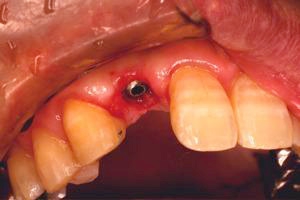

前歯即時埋入症例

術前術前主訴-前歯が腫れて痛い。治療法のうち、ブリッジとインプラントを説明して隣の前歯を削らないですむことからインプラントを選択された。 術前レントゲン術前レントゲン術前レントゲン 抜歯抜歯抜歯を行う。折れていた位置がかなり深い位置であるのがわかる。 歯根も抜歯歯根も抜歯

歯根も抜歯歯根も抜歯歯根も抜歯 抜歯した穴をよく掃除抜歯した穴をよく掃除抜歯した穴をよく掃除(掻爬)後すぐにインプラントを埋入 埋入直後のレントゲン埋入直後のレントゲン埋入直後のレントゲン。上部に見えるのは抜いた歯を利用して両どなりの歯に接着して一時的に使えるようにした。 二次オペ時二次オペ時

仮の支柱を装着仮の支柱を装着仮の支柱を装着 作業模型上のセラミック上部構造作業模型上のセラミック上部構造作業模型上のセラミック上部構造 術後術後術後